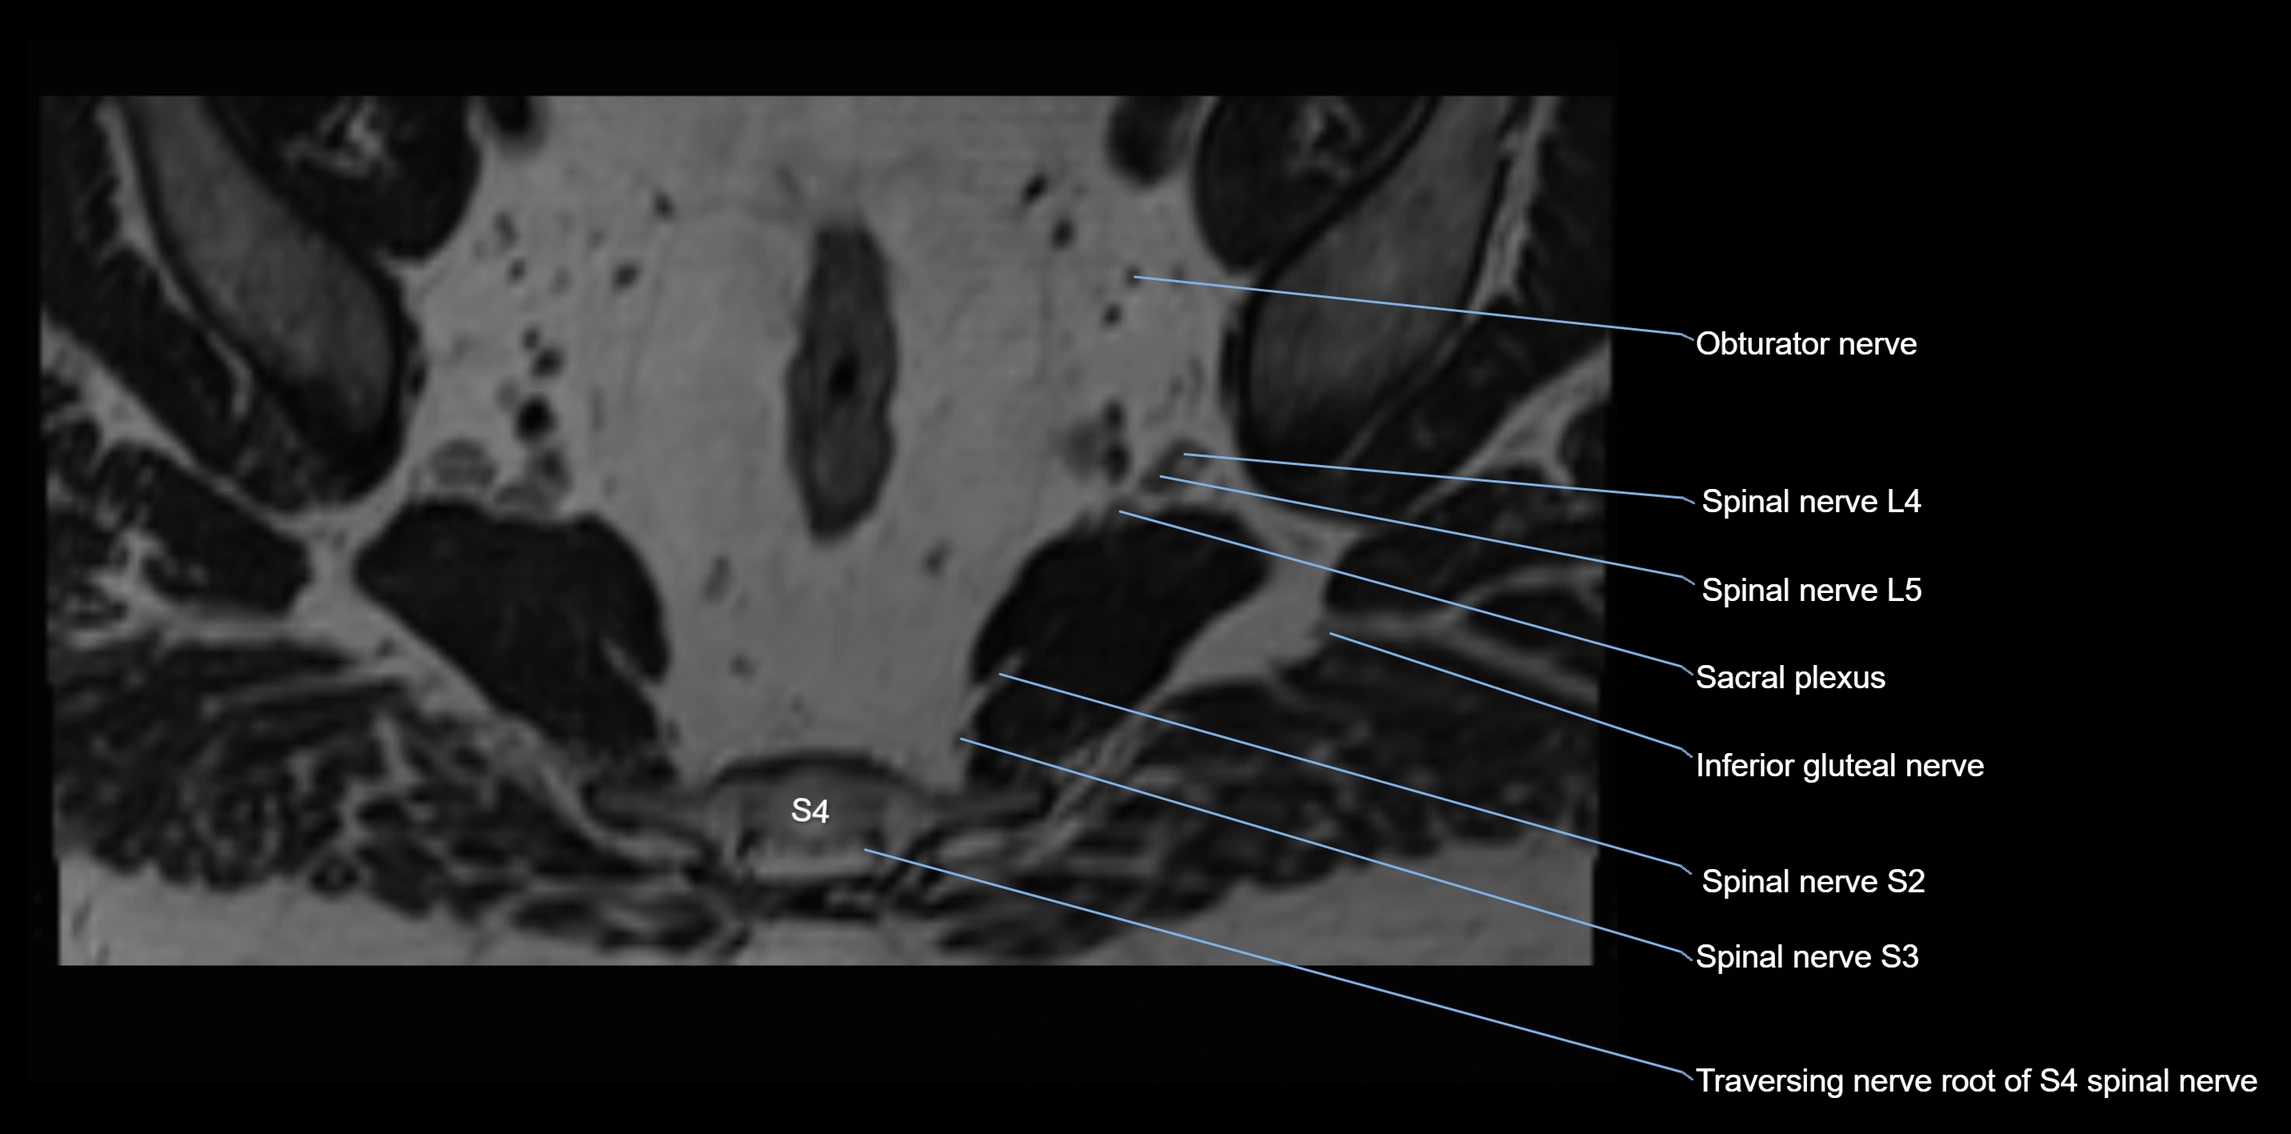

MRI image

image